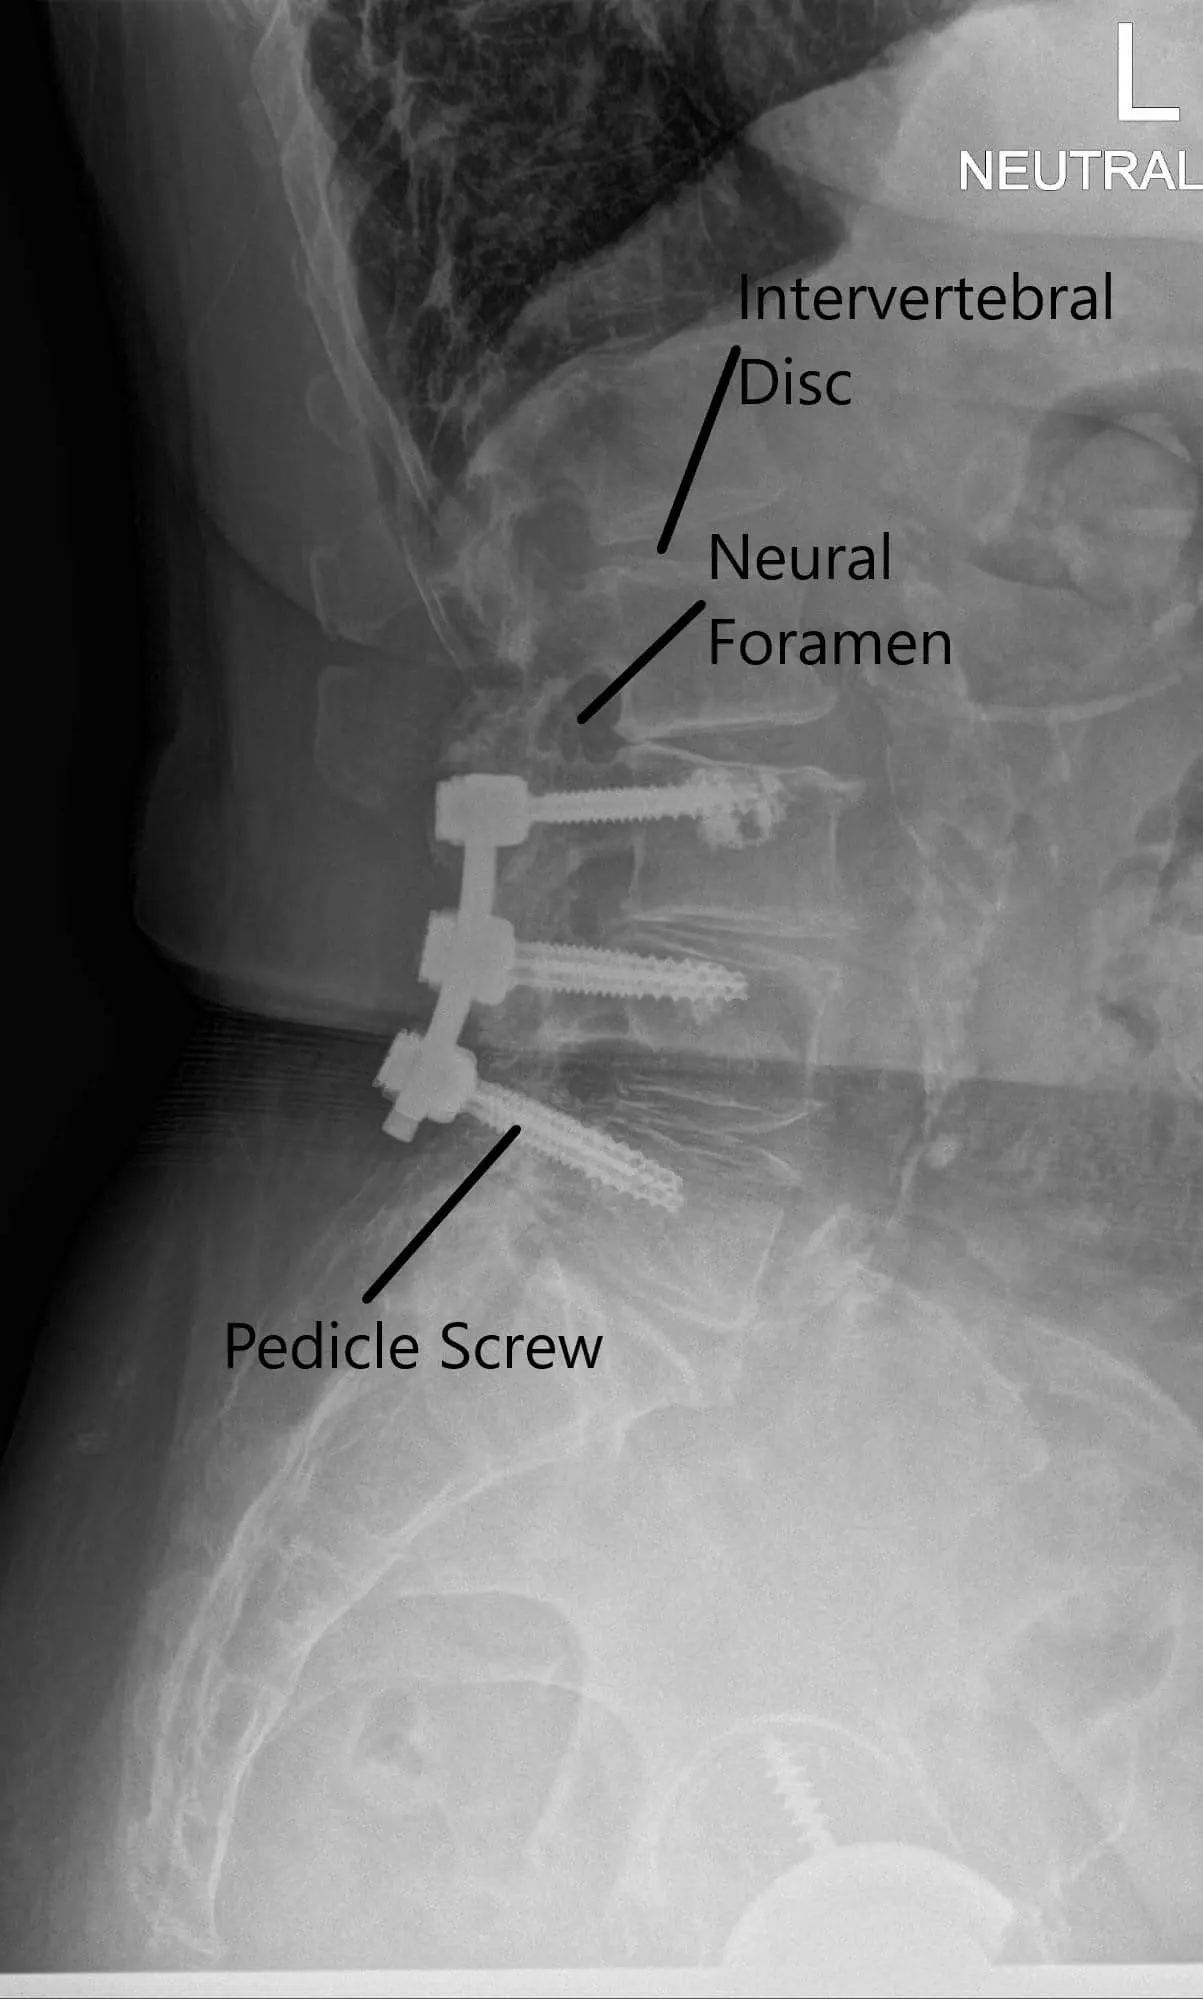

X-ray of the LS spine in AP and Lateral views

X-ray of the LS spine in AP and Lateral views 2

X-ray of the LS spine in AP and Lateral views.

CT scan signs of early screw loosening are seen. However, signs of bony ankylosis from L3-5 are also present. Degenerative spinal stenosis at L2-3 was present and was relatively unchanged since the most recent prior exam in 2018 but demonstrates progressive stenosis over the sequence of scans. MRI showed adjacent segment disease at L2-3 and L5-S1 with nerve root compressions.